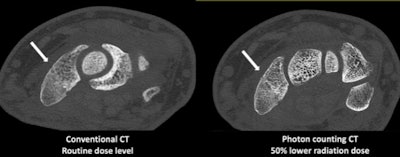

Minnies 2021 winner: Photon-counting CT

For years, photon-counting CT has been a technology that's tantalizing, but still just on the horizon. It now seems that photon-counting CT has finally arrived.

What caused the change? On September 30, the U.S. Food and Drug Administration (FDA) announced it had cleared the first photon-counting CT scanner for commercial marketing (Naeotom Alpha from Siemens Healthineers). In announcing the clearance, the FDA said the scanner was the "first major imaging device advancement" in CT in nearly a decade -- heady words from an agency that's notoriously conservative.

So what's the fuss all about? To understand photon-counting CT, it's useful to first take a step back and look at the technology behind traditional CT detector design. CT images are created by converting x-rays that hit a solid-state CT detector into light; this light is then converted into electrical signals that can be read by a computer and reconstructed into images.

But this is a two-step process that can be inefficient, according to Cynthia McCollough, PhD, of the Mayo Clinic. Since 2014, McCollough has been part of a Mayo team working with Siemens on photon-counting CT and they began using the Naeotom Alpha system earlier this year.

Instead of the two-step process with light conversion, photon-counting CT counts individual x-ray photons as they strike the detector. This provides far more detail about the origin and type of photons, such as whether they are high energy or low energy.

McCollough likens photon-counting CT to water filling a bucket. With conventional CT, there was no way to differentiate whether water filled the bucket drip by drip or in an entire gallon poured in at once. With photon-counting CT, that's now possible.

It has taken decades of work to be able to mass produce the semiconductor material used to perform the one-step detection process. Also, to count individual photons, detector elecronics must be very fast. This explains why it's taken so long for photon-counting CT to become a clinical reality. But now that it is, McCollough is excited about its prospects.

At Mayo, researchers have now performed over 800 scans since 2015 on patients using various iterations of photon-counting CT technology. McCollough sees the technology as being particularly valuable in measuring low-energy x-ray photons, which with conventional CT instrumentation are typically "drowned out" by high-energy photons.

How does this translate into clinical utility? Photon-counting CT can be well-suited to visualizing iodine, which can lead to higher contrast-to-noise ratios and as a result, less contrast media can be used. Scans can also be performed at a lower radiation dose, McCollough said.

On the other hand, radiation and contrast dose can be maintained at the same level as conventional CT, leading to improved visualization of subtle pathology, as well as improvements in lung, musculoskeletal, and vascular images. Even bread-and-butter CT exams like abdominal studies will benefit, she said.